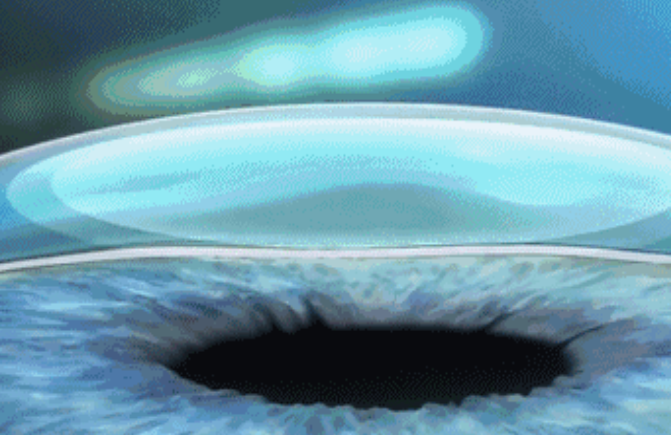

• 暑期特惠 | 全飞秒激光smile3.0近视手术,告别眼镜,迎接高清人生!

暑期特惠 | 全飞秒激光smile3.0近视手术,告别眼镜,迎接高清人生! 2023-06-09